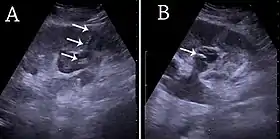

![]() (A) Renal ultrasonograph of percutaneous nephrostomy tube placed through a calyx in the lower pole of a kidney with hydronephrosis. (B) The pigtail catheter is placed in the dilated calyx. The tube in (A) and the pigtail in (B) are marked with white arrows.[1] | |